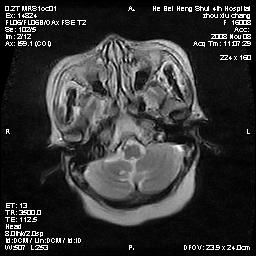

标题: MRI1883:女67岁,半年前曾患脑梗塞,治疗后好转,近3各月精 [打印本页]

女67岁,半年前曾患脑梗塞,治疗后好转,近3各月精神恍惚。

形态及整体病灶看起来首先考虑转移瘤或淋巴瘤,但奇怪的是多个病灶周围均未见显著的水肿区,这不符合这两个肿瘤的特点,结合ct表现及患者病史有个人考虑是否有皮层下动脉硬化性脑病伴多发胶质增生可能.

1皮层下动脉硬化性脑病,2胶质增生。

皮层下动脉硬化性脑病伴脱髓鞘改变!